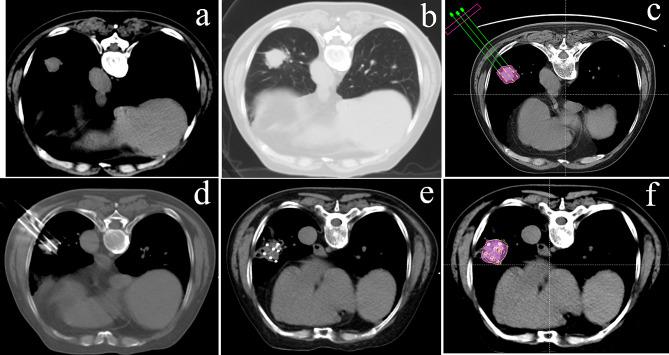

Patients with early-stage (T1-T2aN0M0) NSCLC who underwent CT-guided SABT or MWA between October 2014 and March 2017 at four medical centers were retrospectively analyzed. Survival, treatment response, and procedure-related complications were assessed.

A total of 83 patients were included in this study. The median follow-up time was 55.2 months (range 7.2-76.8 months). The 1-, 3-, and 5-year overall survival (OS) rates were 96.4%, 82.3%, and 68.4% for the SABT group (n = 28), and 96.4%, 79.7%, and 63.2% for MWA group (n = 55), respectively. The 1-, 3-, and 5-year disease-free survival (DFS) rates were 92.9%, 74.6%, and 54.1% for SABT, and 92.7%, 70.5%, and 50.5% for MWA, respectively. There were no significant differences between SABT and MWA in terms of OS (p = 0.631) or DFS (p = 0.836). The recurrence rate was also similar between the two groups (p = 0.809). No procedure-related deaths occurred. Pneumothorax was the most common adverse event in the two groups, with no significant difference. No radiation pneumonia was found in the SABT group.